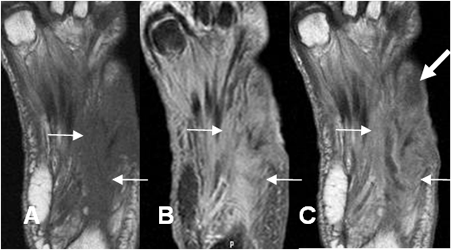

Fig 125 C. Pie diabético.

A: RM axial en T1 simple, B: RM axial en STIR y C: RM axial en T1 con contraste.

Pie diabético con cambios inflamatorios en los músculos plantares, hipointensos en T1 e hiperintensos en STIR. (Flechas delgadas). Con el contraste hay zona que no realza, sobre el 5º metatarsiano, por la presencia de tejido desvitalizado. (Flecha gruesa).